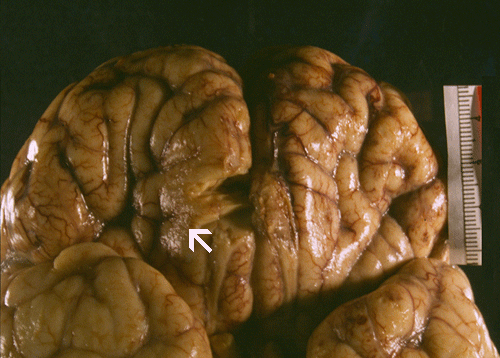

Gross pathology: The brain weighs 1,650 grams (normal is 1,320 grams and was grossly edematous. The leptomeningeal surface appears slightly granular and this feature is best appreciated on side lighting (Arrow in Panel A). On coronal sections, the lateral ventricles are totally collapsed and the sulci are flattened out by the edema. There are some poorly defined brownish, round patches in the cortex and thalamus. The uncal notch on the left side (Panel  B) appears deep, brownish and friable whie the uncal notch in the right side appear deep. There are focal necrosis in the orbital frontal lobe, bilateral olfactory bulbs, and bilateral temporal lobes.

The brain is extremely edematous and therefore heavy as illustrated in our case. The extreme edema will produce uncal and tonsillar herniation which is usual cause of death. There is a thin layer of purulent exudates on the leptomeninges. On cross sections, small hemorrhagic foci can be observed.